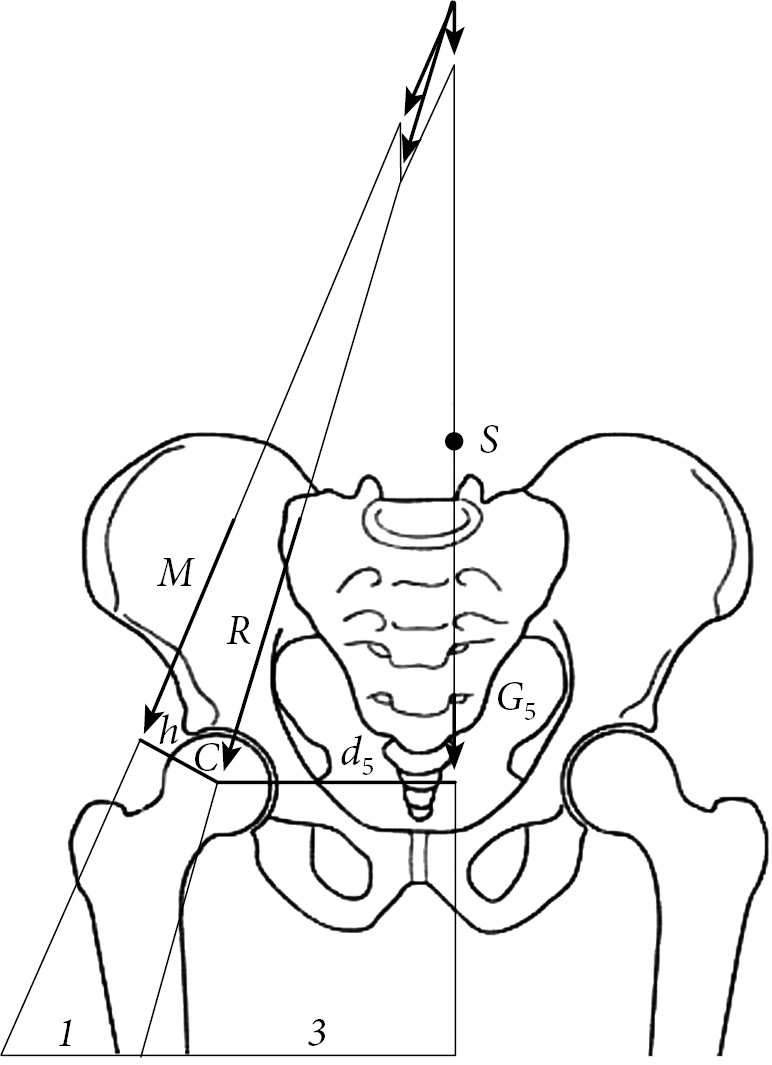

A completely different picture is seen when a person is standing on one limb. In this case, the hip joint retains a partial body weight (head + body + two arms + leg weight in the step transfer position). When single-support standing, muscle forces act that prevent the pelvis from tipping over (Fig. 2).

Fig. 2. Schematic representation of the load on the hip joints when a person is standing on the right limb (according to Pouwels)

In this case, the leverage system operates by the equation of vectors: hMr = d5G5t. Point S of the vertically acting partial body weight G5 is shifted to the side of the leg, which is in the transferable period of the step. The lever of the person’s load arm is d5. On the side of the leg on which the person stands, the resulting M (abductor forces) acts with a lever arm of size h. For this reason, the partial weight of the body G5 on the side of the leg in the position of the transferable period of the step causes a moment of rotation around the femoral head (d5G5t), and it is counteracted by the moment of rotation of the muscular strength of the contralateral side (hMr). As a result, a system of balancing levers is formed: hMr = d5G5t. Pauwels found that the lever arm d5 is three times longer than the lever arm h of muscle strength M. As a result, the muscle strength of the abductors must be three times greater in order to maintain body balance. The resulting R should be approximately four times greater than the partial bodyweight of G5.

Pauwels performed similar calculations not only on healthy joints but also with coxa valga. The author concluded that with an increase in the collum-diaphyseal angle, the value of the total resulting R increases, which entails an increase in the load on the joint.

In a healthy person, bodyweight is transferred to the hip joints evenly and at an angle of 45°. With a unilateral CHD, the vertical center of gravity passes closer to a healthy limb. When single-support standing, a person walks with a limp until the hip approaches as close as possible to one of the points of the pelvis. This moment of walking is called the dead phase of the step (Fig. 3). At the same time, pelvic-trochanter muscles keep the pelvis from tipping over in the horizontal plane. Can such a patient be helped in order to stabilize the hip joint and improve gait?

Fig. 3. Schematic representation of the dead phase of step d

We hypothesized that elimination of the dead phase of a step in a particular adolescent is possible by means of an extra-articular lengthening transversal osteotomy of the hip (patent No. 2614101). Therefore, the primary aspect of surgical intervention for CHD is the correct choice of the support point for the pelvis.

To do this, two X-ray functional images should be taken. The first image of the hip joint meets the generally accepted standards for anteroposterior projection in the supine position of the patient. On the roentgenogram, we assess the degree of development of neoarthrosis and the level of spatial location of the femoral head. The second X-ray of the hip joint is performed in the position of the patient standing with the support of the affected limb. On the radiograph, we evaluate the severity of the symptom of the longitudinal slide of the femoral head and find the point of maximum approximation of the femur to the pelvis. In this case, we form a triangle ABC, where d is the dead phase of the step (Fig. 3).